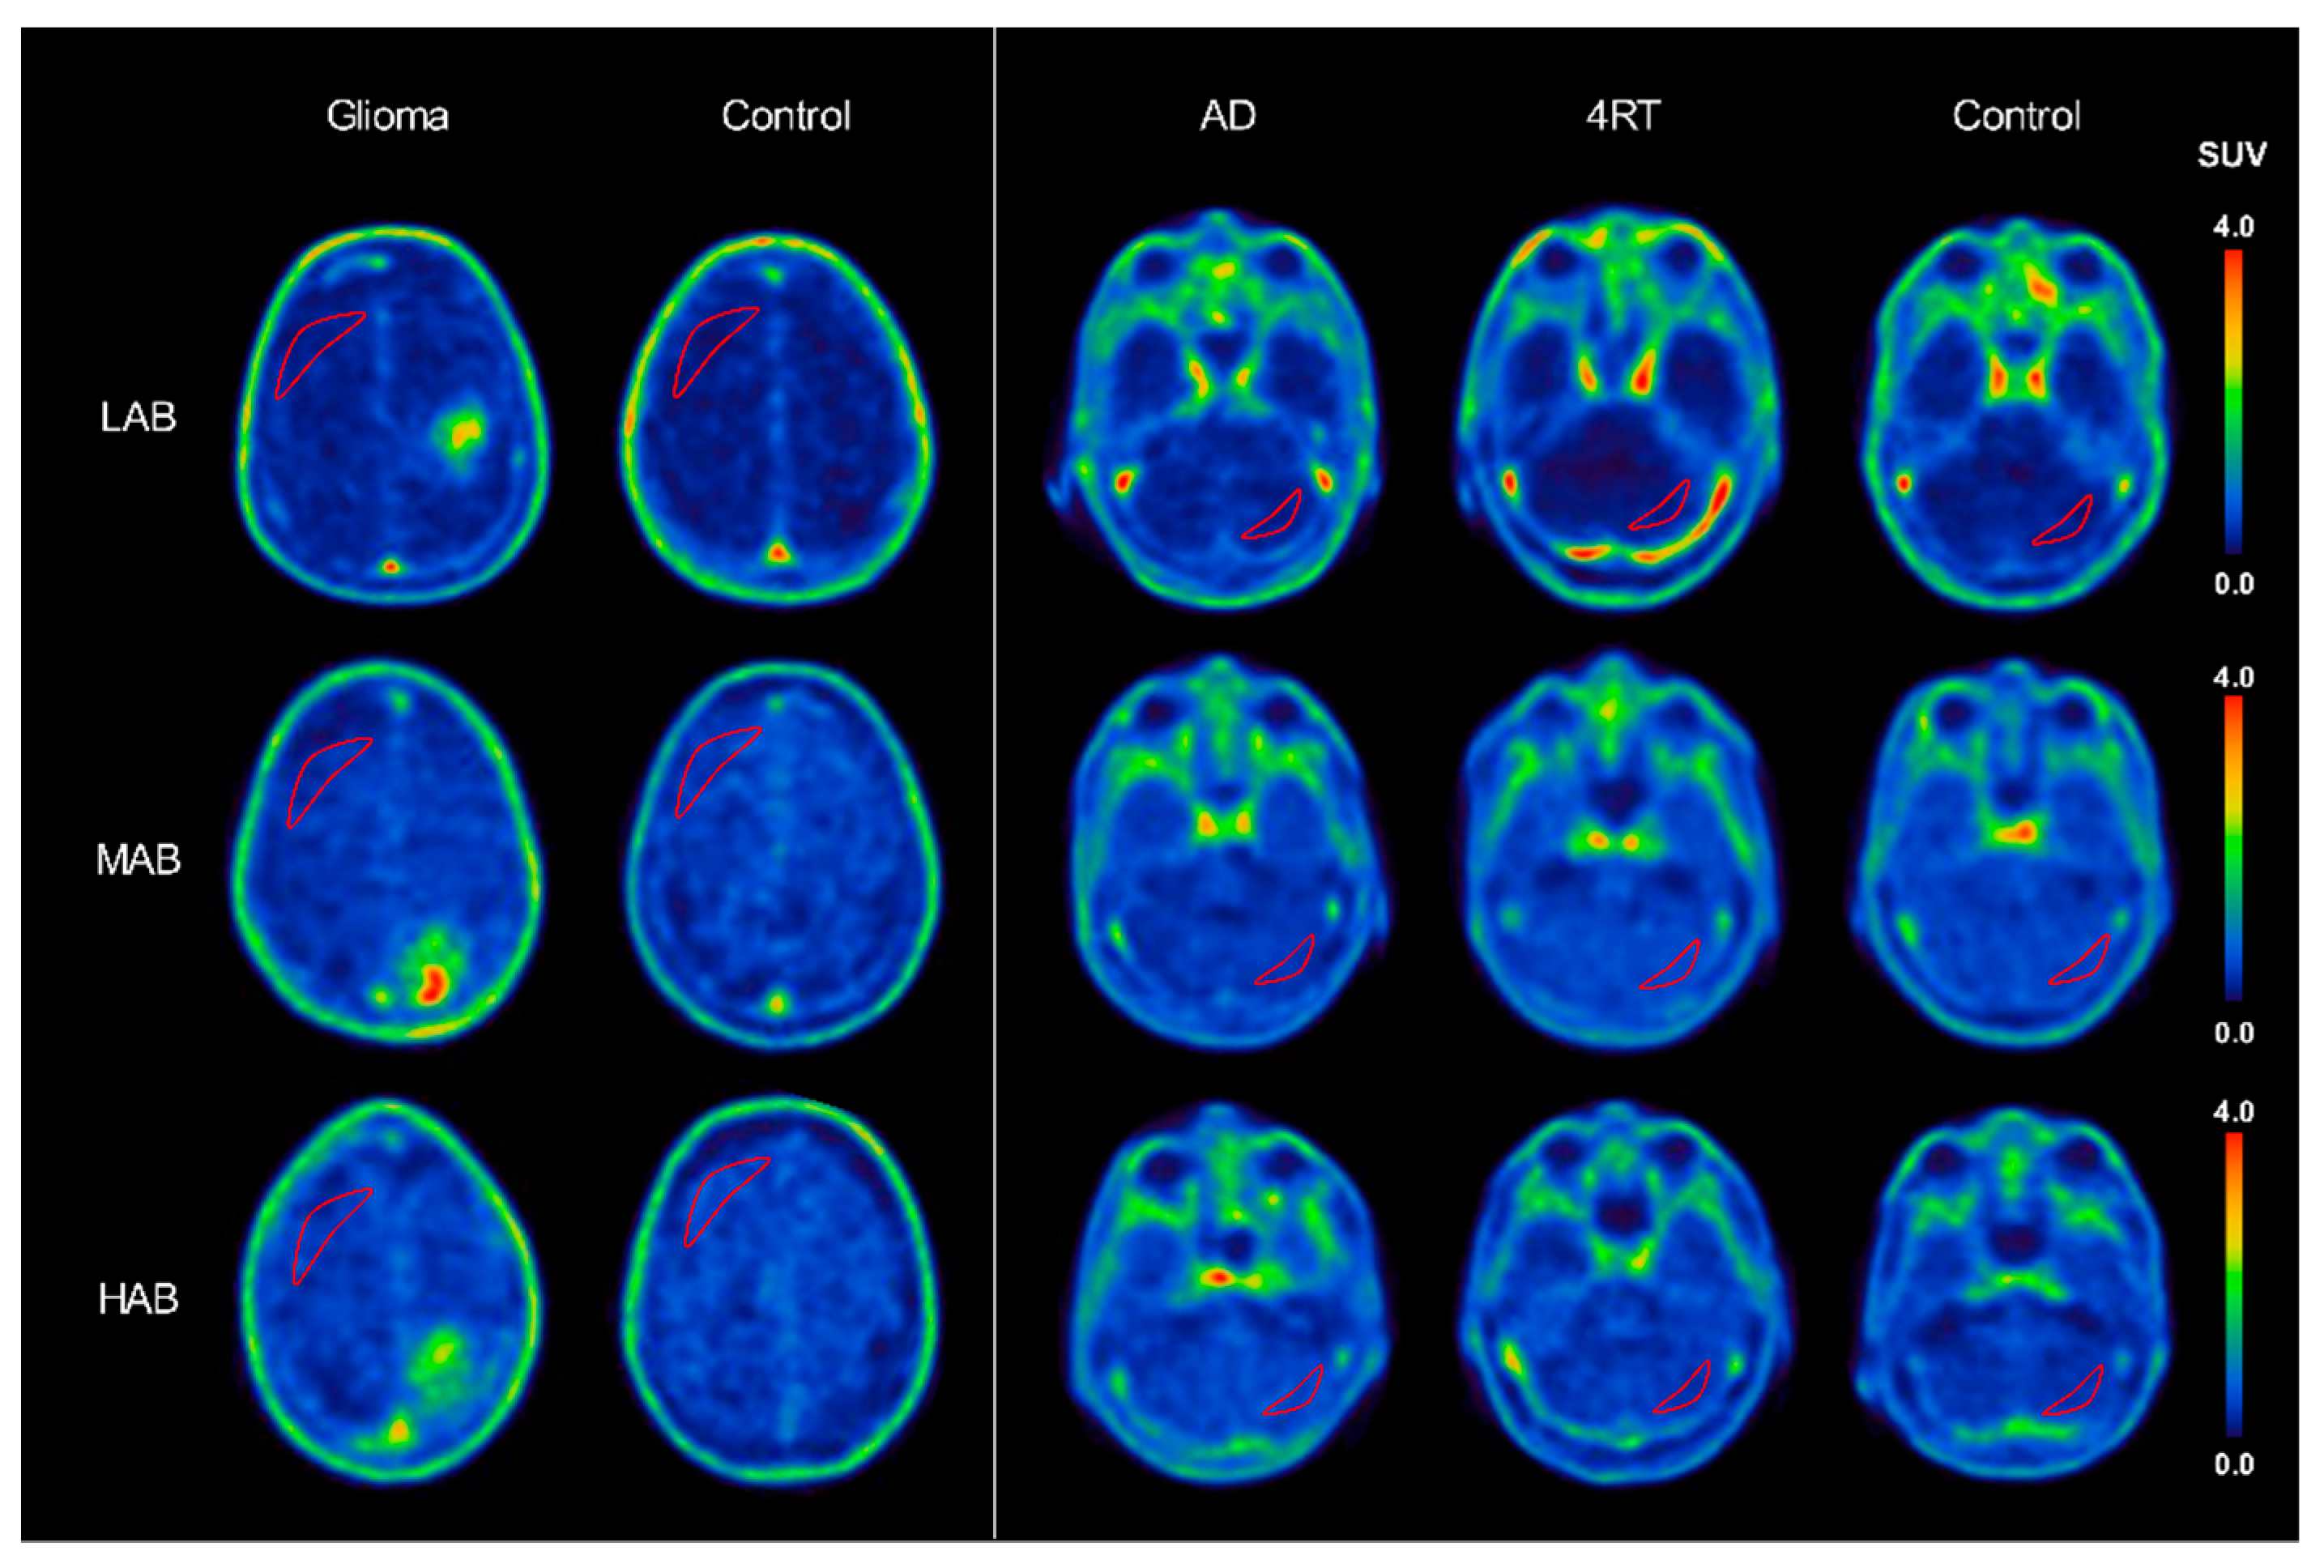

2.2. [18F]GE-180 Binding in a Comparison of rs6971 Polymorphism Subgroups

2.2.2. Disease Groups

Glioma

4RT

AD